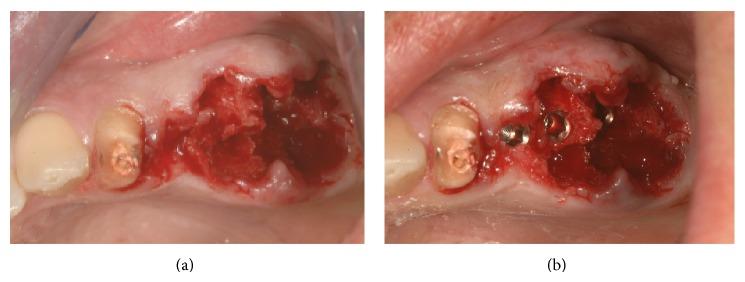

The extraction of teeth results in rapid bone resorption both vertically and horizontally in the first month. The loss of alveolar ridge reduces the chance of implant rehabilitation. Atraumatic extraction, implant placement in extraction socket, and an immediate prosthesis have been proposed as alternative therapies to maintain the volume and contours tissue and reduce time and cost of treatment. The immediate load of implants is a universally practiced procedure; nevertheless a successful procedure requires expertise in both the clinical and the reconstructive stages using a solid implant system. Excellent primary stability and high bone-implant contact are only minimal requirements for any type of implant procedure. In this paper we present a case report using a new type of implants. The new type of implants, due to its sophisticated control system of production, provides to the implantologist a safe and reliable implant, with a macromorphology designed to ensure a close contact with the surrounding bone.